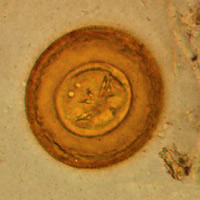

A: Egg

of Hymenolepis diminuta. These eggs are round or slightly oval, size 70

to 86 µm by 60 to 80 µm, with a striated outer membrane and a thin inner membrane. The

space between the membranes is smooth or faintly granular. The oncosphere has six

hooks (of which at least four are visible at this level of focus).

Image contributed by Georgia Department of Public Health.